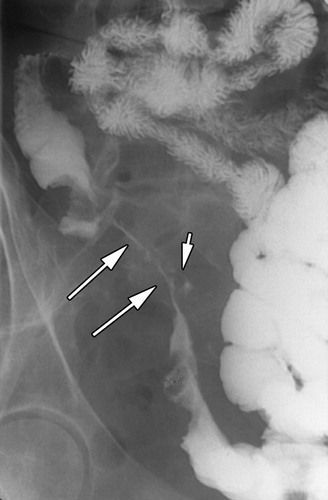

String Sign in Crohn's Disease

This x-ray shows "string sign" in a patient with crohn's disease due to luminal narrowing of the terminal ileum.